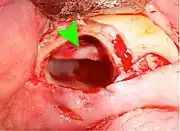

Wisdom teeth removal

Wisdom teeth removal (extraction) is the most common treatment for impacted wisdom teeth. In the US, 10 million wisdom teeth are removed annually.[20] The procedure can be either simple or surgical, depending on the depth of the impaction and angle of the tooth. Surgical removal is to create an incision in the mucosa of the mouth, remove bone of the mandible or maxilla adjacent the tooth, extract it or possibly section the tooth and extract it in pieces. This can be completed under local anaesthetic, sedation or general anaesthetic.[5] As of 2020, the evidence is insufficient to recommend one type of surgical practice over another.[21]